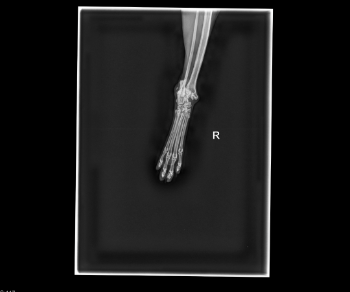

Unser geliebter Kater Maxi wurde angefahren und muss dringend operiert werden. Er erlitt einen schweren Beinbruch und leidet.

Unser wundervoller Kater braucht dringend eine Operation. Sein Beinchen muss operiert/evtl. amputiert werden. Bitte hilft uns mit das durchzustehen.